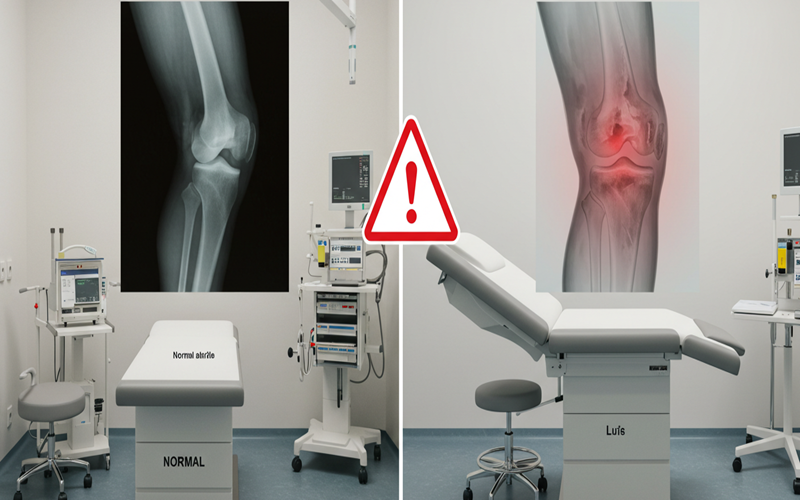

무릎 소리가 단순한 마찰음인지, 아니면 관절 질환의 신호인지를 구분하는 것이 가장 중요합니다.

종류 | 특징 |

---|---|

걱정하지 않아도 되는 소리 |

뚝, 두둑, 뼈가 부딪히는 소리 등. 통증, 붓기, 열감, 잠김(무릎이 펴지지 않음) 등의 증상이 전혀 없음. |

위험 신호일 수 있는 소리 |

사각사각, 우두둑, 맷돌 갈리는 소리 등. 소리와 함께 통증, 붓기, 열감, 불안정성, 혹은 무릎이 걸리는 듯한 느낌이 동반됨. |